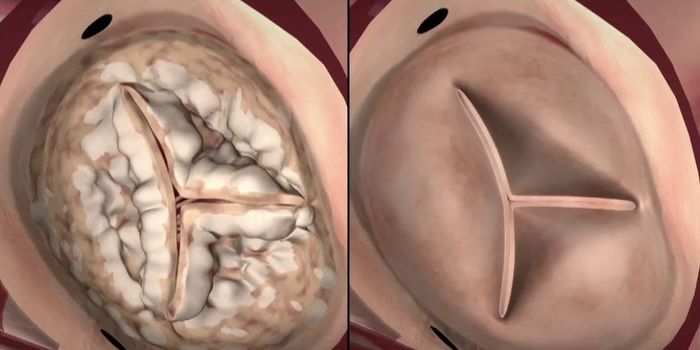

FEB 15, 2017CardiologyThe heart’s four chambers, made up of left and right atria and ventricles, work together in an amazingly intricate ...